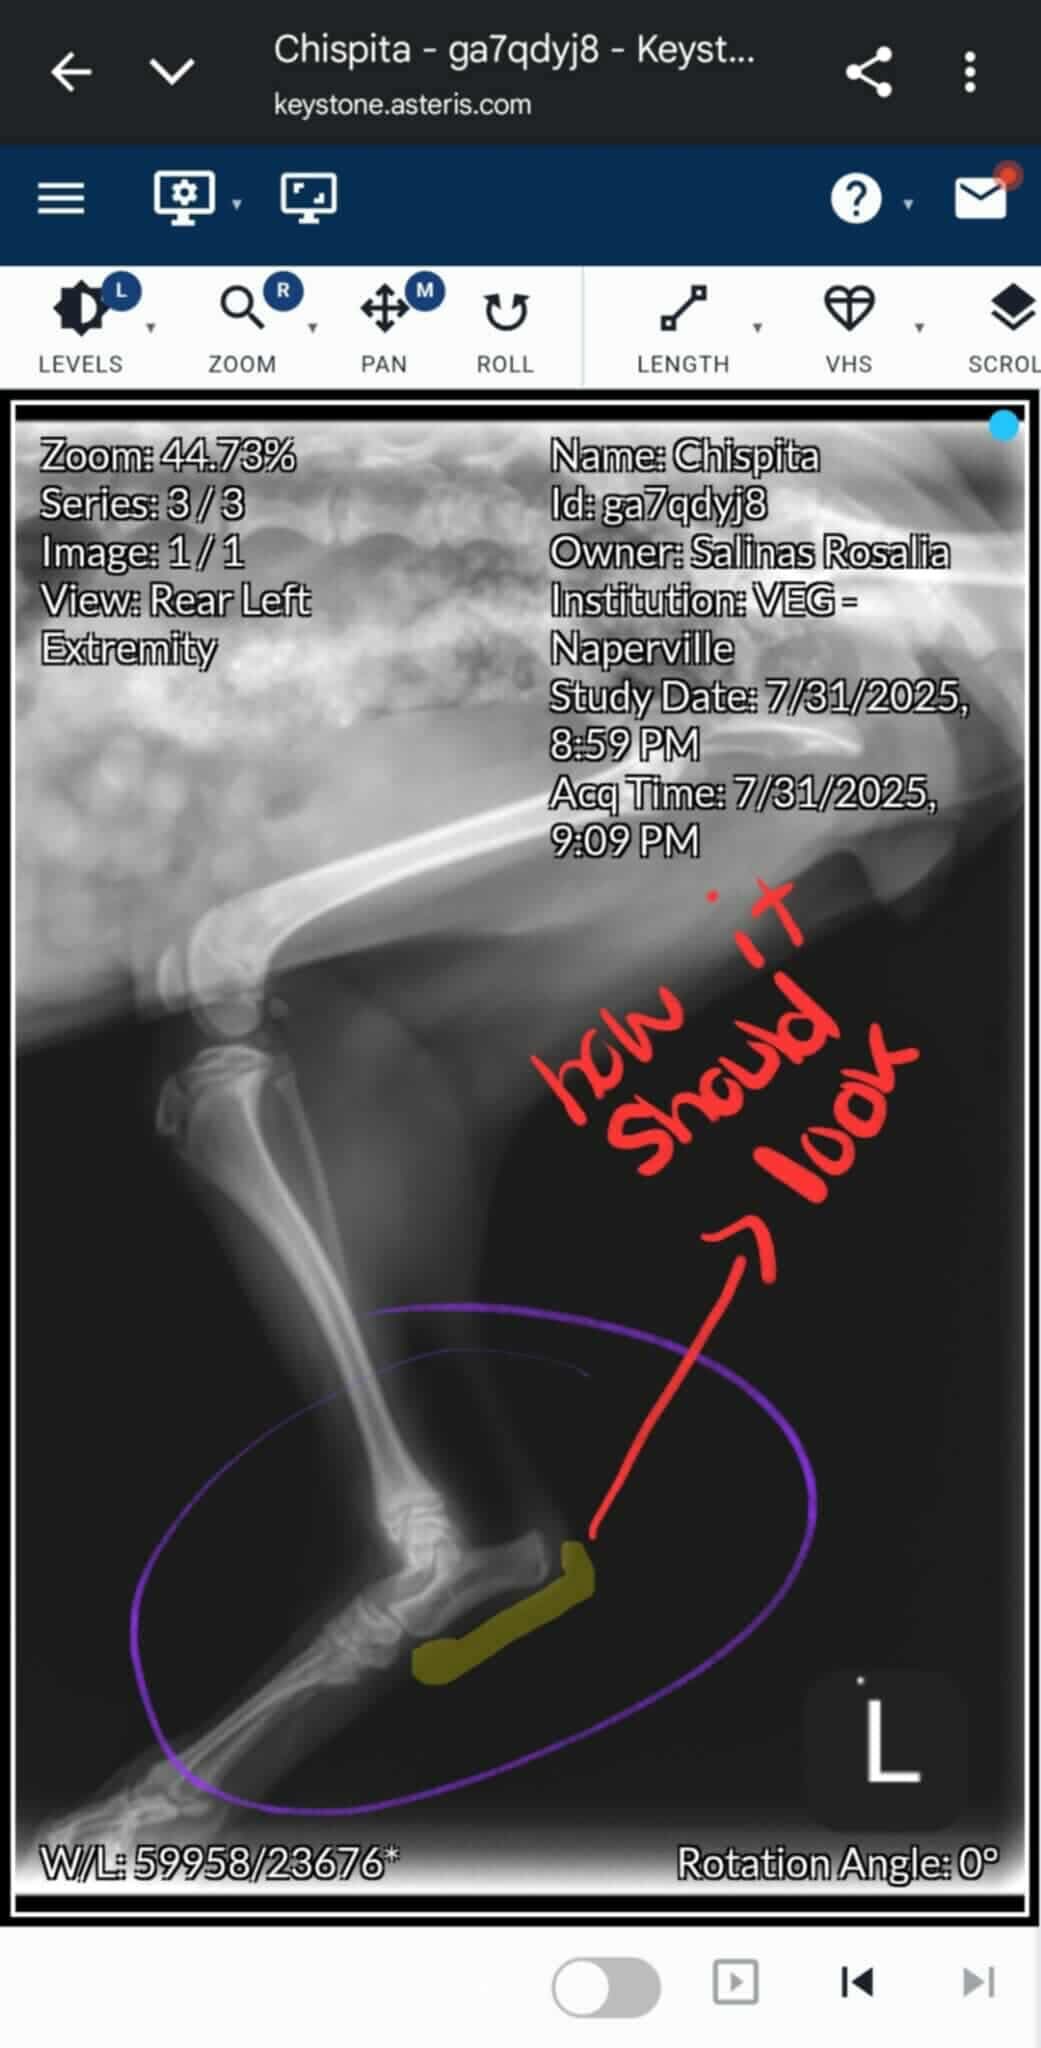

Chispita is my sister’s beloved 6-month-old yorkie mix puppy, and she’s always been a source of joy and comfort for their family. Recently, Chispita suffered a broken heel and now can’t walk or play like she used to. It’s heartbreaking to see her in pain, especially knowing how much she means to my sister and her two young children.

My sister is the only provider for her family. Her partner recently lost his job, and with two kids to care for, covering the cost of Chispita’s urgent surgery is overwhelming. The veterinarians have said that Chispita needs surgery as soon as possible to repair her heel. Without it, she may lose her leg. My sister has already spent a lot on initial exams and treatment, but the surgery and follow-up care are more than she can manage alone right now.

Chispita es la perrita mestiza de yorkie de 6 meses de mi hermana, y siempre ha sido una fuente de alegría y consuelo para su familia. Recientemente, Chispita sufrió una fractura en el talón y ahora no puede caminar ni jugar como antes. Es desgarrador verla con dolor, especialmente sabiendo cuánto significa para mi hermana y sus dos hijos pequeños.

Mi hermana es la única proveedora de su familia. Su pareja perdió recientemente su trabajo y, con dos niños a su cargo, cubrir el costo de la cirugía urgente de Chispita es abrumador. Los veterinarios han dicho que Chispita necesita la cirugía lo antes posible para reparar su talón. Sin ella, podría perder la pierna. Mi hermana ya ha gastado mucho en exámenes y tratamientos iniciales, pero la cirugía y el cuidado posterior son más de lo que puede manejar sola en este momento.